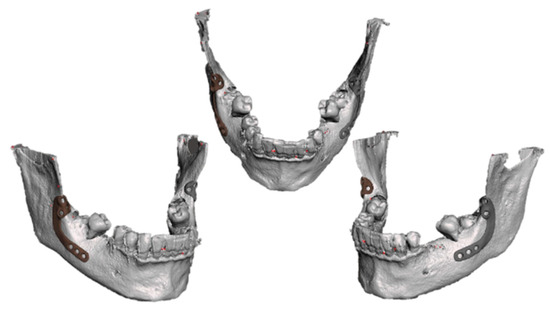

2.3. Design and Manufacturing of Customized Titanium Plates